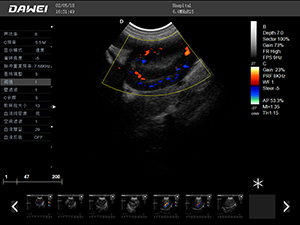

F5-VET彩色多普勒動物超聲診斷儀

F5-VET是一款性能可靠的獸用全數字彩色多普勒超聲診斷系統,基于Windows平臺 配置固態盤快速啟動 穩定可靠,融合了全面豐富的臨床應用,結合優異的人機工程學設計,推動了臨床診斷新趨勢。

·中小動物的肝、膽,脾、腎、膀胱、子宮、妊娠等各組織器官的檢查和病變的診斷